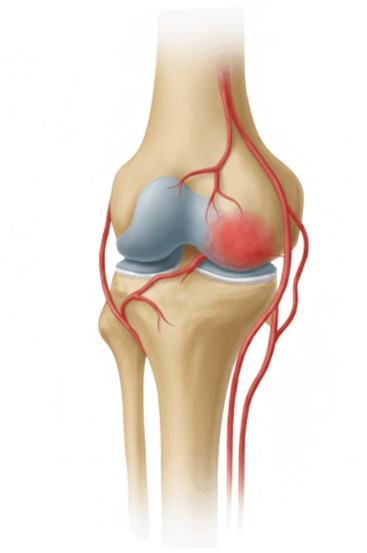

GAE is a novel, image-guided treatment developed to relieve chronic knee pain by blocking abnormal blood vessels in the joint. The procedure involves injecting tiny embolic agents—such as particles or coils—into specific genicular arteries, thereby reducing excess blood flow that fuels inflammation and pain.

In osteoarthritic joints, abnormal neovascularization—the formation of new, fragile blood vessels—plays a key role in inflammation and pain. GAE targets these vessels with precision:

- Step 1: Under angiographic guidance, the interventional radiologist maps the network of genicular arteries that supply the inflamed joint.

- Step 2: Embolic materials are introduced to selectively block these vessels.

- Step 3: Blood flow to the painful areas is reduced, leading to less inflammation and pain.

Why Anatomy Matters

Success depends heavily on the operator’s detailed knowledge of genicular artery anatomy, including its variations. Accurate targeting helps maximize efficacy and minimize risks like non-target embolization.